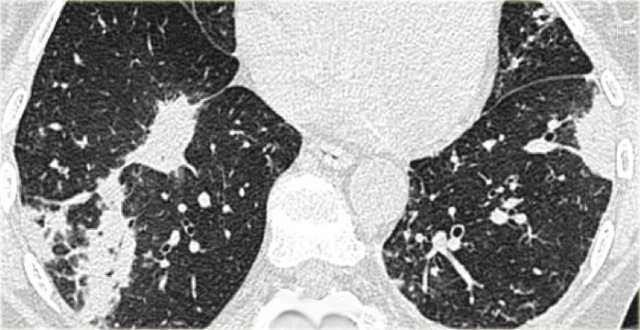

On the left typical features of cardiogenic pulmonary edema

There is smooth septal thickening and some ground glass opacity in the dependent part of the lungs.

In addition there is bilateral pleural fluid.

In a patient with a known malignancy lymphangitic carcinomatosis would be high in the differential diagnostic list.